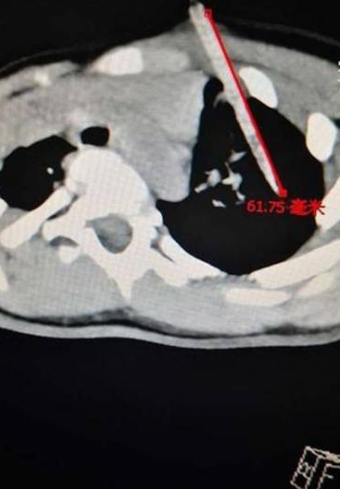

楚天都市报9月17日电。近日,武汉荒坡盘龙城,刘女士的2岁女儿吃炸物时不小心摔倒,导致竹签从左胸扎进肺部,深达6厘米。“五分钟没看住,意外就发生了。”回想起一周前发生的事,仍后怕不已。